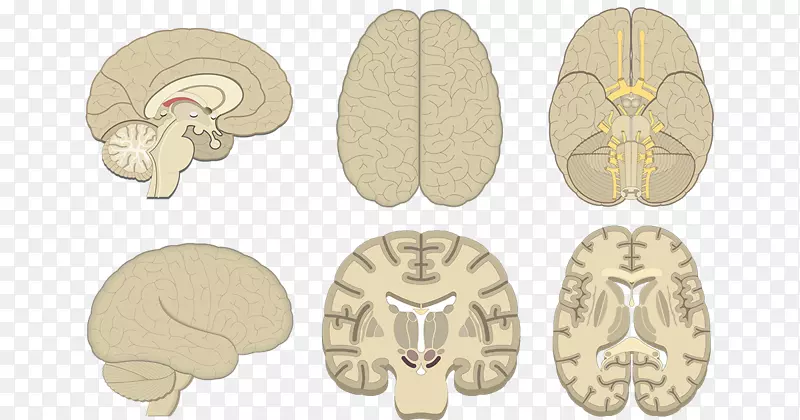

大脑冠状面和矢状面结构分解图PNG图片素材下载_图片编号2533656-PNG素材网。

脳 MRI 3D : 正常解剖学e-Anatomy。